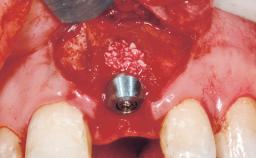

Type of Implants One-Piece|Reduced-Diameter

Bone Augmentation Horizontal|Staged

Augmentation Materials Autogenous chips|Membrane

Placement Protocol Early or late implant placement